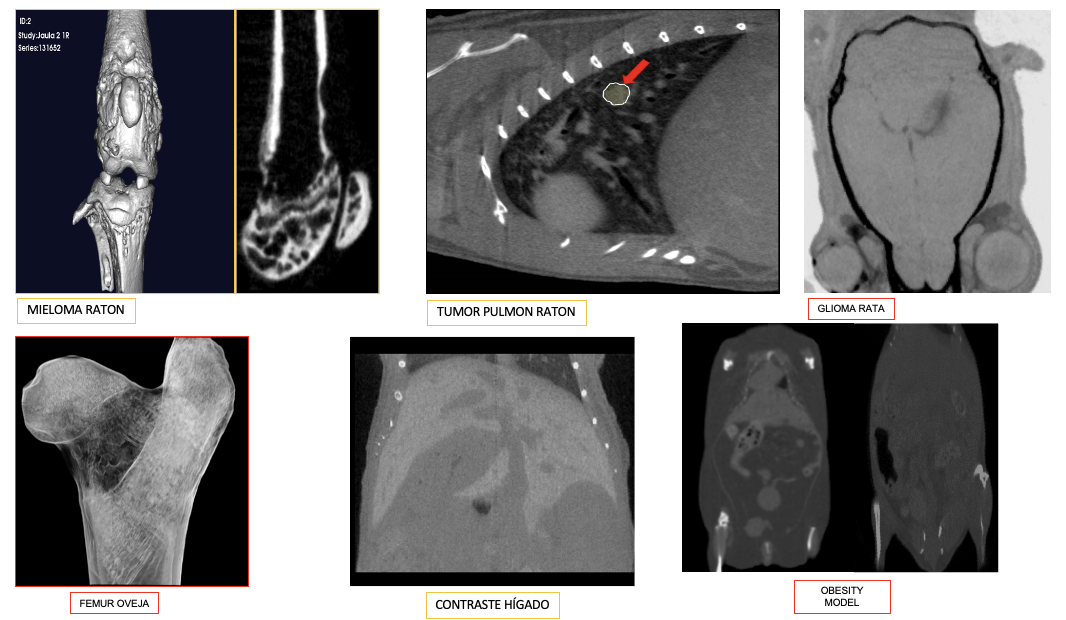

• Tomografia Micro-TAC: Quantum FX, REVVITY

• Resolució espacial: fins a 10 µm, permetent una visualització detallada d’estructures òssies i teixits tous. Estudi d’escaneig ràpid en 17 segons.